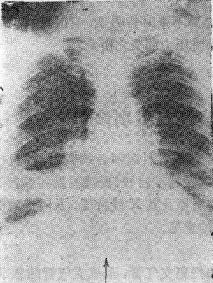

2.支气管腔外压性梗阻 如淋巴结肿大血管环压等图115-1右下肺不张

右下肺不张

图115-1 右下肺不张